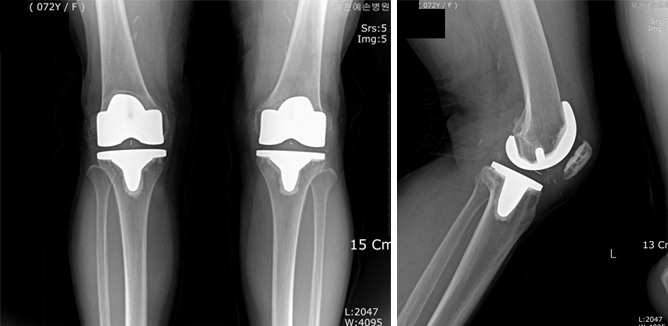

무릎 인공관절 수술은 많은 사람들이 고통받고 있는 관절 질환을 효과적으로 치료하는 방법 중 하나입니다. 이 수술을 통해 많은 환자들이 통증에서 벗어나 보다 나은 삶의 질을 누릴 수 있게 됩니다. 하지만, 수술 후 회복 과정은 개인마다 매우 다를 수 있으며, 회복 기간 동안 환자는 신체적, 정서적, 사회적 변화에 직면하게 됩니다. 이 블로그 포스트에서는 무릎 인공관절 수술 이후의 회복 기간을 단계별로 나누어 자세히 설명하고, 각 단계에서 어떤 점을 유의해야 하는지 알아보겠습니다. 따라서, 무릎 인공관절 수술을 고려하는 분들이라면 이 글이 큰 도움이 될 것입니다. 궁금한 점이 있거나 추가 정보가 필요하다면 아래의 버튼을 클릭해 주세요.